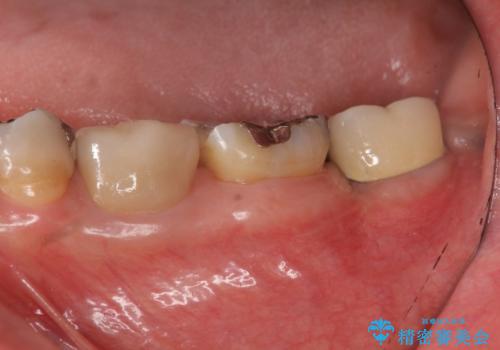

深い虫歯により抜歯となった奥歯 インプラント治療でかみ合わせを回復する